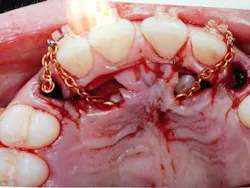

When a full permanent dentition is present (with the exception of impacted canines), the labial/palatal position of the canine will have an influence on what the provider can do. (1) Arguably, obtaining a CBCT is considered mandatory and will allow for a more inclusive treatment plan creation. If angulation is favorable, then consideration to remove the primary canine and wait six months to see if there is movement of the permanent canine is an option. If extraction of the canine(s) is needed, then a premolar substitution, which is dependent on occlusion, can be used in the space. An implant can also be an appropriate alternative. When pulling a canine into the occlusal arch, there is risk involved. Trauma to adjacent teeth (root resorption) and ankylosis are some of the most common complications.The patient was put in full orthodontics and referred to a surgeon for extraction of the primary canines, exposure, and placement of retention on the impacted canines to pull them directly down from their current position.

A ballista appliance was used to prevent a facial pull of the canines in order to avoid and prevent resorption of the roots of the lateral incisors. As movement progressed over the course of the next year, eruption of the canines was considered a success. Once in position, they will be pulled facially into occlusion.